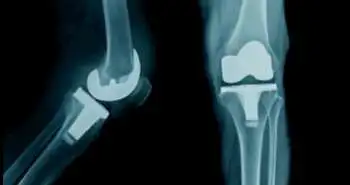

Impact of oral osteoarthritis therapy usage among other risk factors on knee replacement (KR): a nested case-control study using the Osteoarthritis Initiative cohort

The present case-control study was aimed to determine the relatedness between exposure to commonly used oral OA therapies and relevant confounding risk factors related to the occurrence of knee replacement (KR), using the Osteoarthritis Initiative (OAI) database.

The present study demonstrated that exposure to some of the commonly used oral OA therapies, i.e. NSAIDs, COX-2 inhibitors, acetaminophen, narcotics, or glucosamine/chondroitin sulfate, in a period of 2– 5 years, was not correlated with the occurrence of KR when compared to no exposure to such medications. Many other risk factors including race, level of symptoms, and BMI were identified as being linked to KR.  The findings also revealed the neutral effect of oral medications on knee replacement controlling the most important confounding factors that promote such occurrences: clinical demographics, symptom severity, socioeconomic status, radiographic grading, and structural changes assessed by quantitative MRI. The clinical and sociodemographic data of our study population exhibits similarity with previous studies exploring the role of disease treatment on KR, but it does not explain the discrepancy in the effect of such NSAIDs. The study also established the use of KR as a sole marker and a logical outcome of disease progression. Indeed, MRI parameters evaluated in knee OA, such as the medial compartment cartilage volume/thickness, can also consistently predict outcomes such as KR. The cartilage volume at index (KR) time was also similar in both groups indicating a balance between the factors leading to the progression of cartilage volume loss up to KR in both the groups.